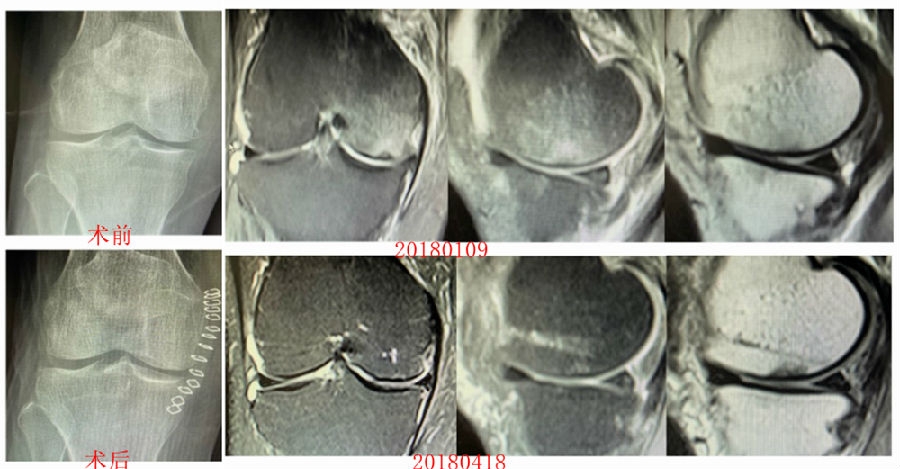

病例1:女,65岁,主诉右膝关节内侧疼痛1周。2018年1月X光未见右膝骨质异常,MR检查见股骨内侧髁骨坏死,半月板相对突出百分比(RPE)28.99%,关节线会聚角1.4°。

予切开行克氏针钻孔减压,口服消炎止痛药物、钙剂及骨化三醇,不负重6周,后改部分负重至3个月。2018年4月复查MR见骨髓水肿基本完全吸收,坏死区局限并修复良好,半月板相对突出百分比(RPE)32.08%,患者临床症状消失。

病例2:女,69岁,主诉左膝关节内侧疼痛1月余。2017年11月X光见右膝股骨髁负重区的软骨下区域出现了椭圆形透亮影,MR检查见股骨内侧髁骨坏死,合并内侧半月板外突和后角层裂,半月板相对突出百分比(RPE)25.32%,矢状位病变区域前后径为23.96mm,关节线会聚角6°。

予克氏针钻减压,消炎止痛药物口服、静滴唑来膦酸钠注射液,避免负重6周,后改部分负重至3个月,患者依从性差。2018年1月复查MR见骨髓水肿少许吸收,坏死区扩大,半月板相对突出百分比(RPE)33.53%,矢状位病变区域前后径为26.89mm,患者仍有膝关节疼痛症状,建议行手术治疗,患者拒绝手术后失访。

病例3:男,70岁,主诉右膝关节疼痛1年余。查体右膝无肿胀畸形,膝活动度0-120°,内侧间隙压痛。

已经累及44%的股骨内侧髁病变,半月板轻度突出,内侧后角水平撕裂

MRI上深度>20mm

治疗选择保守还是手术?

保守治疗4个月后复查

保守治疗后效果欠佳,坏死范围扩大、塌陷

翻修手术选择截骨矫形还是单髁置换?

最终选择截骨矫形

术后1年1个月

术后2年1个月拆钉

内侧半月板突出未见明显进展